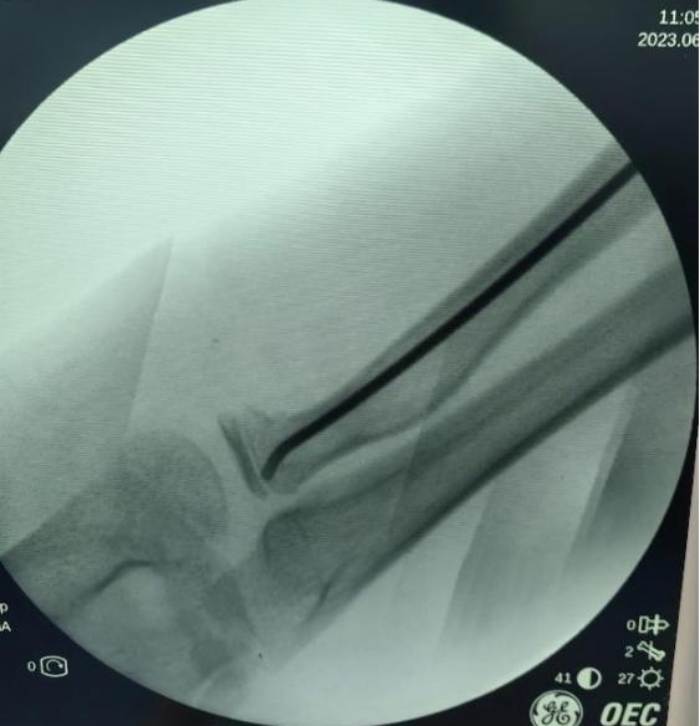

X線(xiàn)顯示:橈骨頸骨折端成角大于30°。骨科主任醫(yī)師錢(qián)鈞提醒,這種情況下后期發(fā)育畸形的可能性大,建議手術(shù)治療。

錢(qián)鈞組織骨科團(tuán)隊(duì)研討手術(shù)方案,決定為毅毅實(shí)施“橈骨頸骨折閉合復(fù)位彈性髓內(nèi)針內(nèi)固定術(shù)”。

采用該術(shù)不用切開(kāi)骨折端,創(chuàng)傷小,切口僅為1.5cm,術(shù)后疤痕小,不影響美觀,且手術(shù)時(shí)間短,固定穩(wěn)妥,利于肢體功能恢復(fù)。術(shù)后第2天毅毅即順利出院。